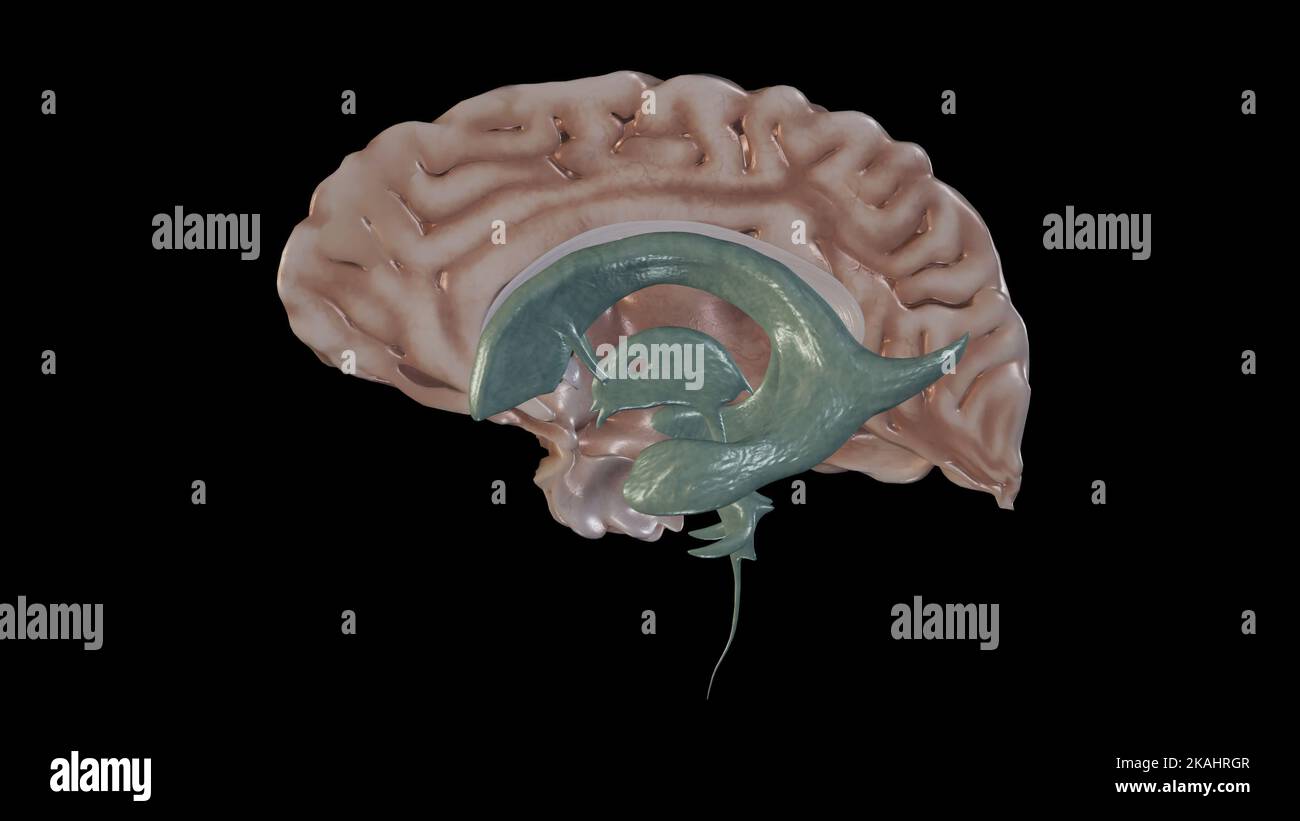

RF2T7NGWK–Ventrikel und zerebraler Aquädukt lateral in Farben Röntgenbild-3D-Rendering-Illustration. Menschliches Gehirn und Ventrikelsystem Anatomie, medizinisch, gesund

RM2AWF8JC–Die Anatomie des Nervensystems, vom Standpunkt der Entwicklung und Funktion. -Ant. HornCentra, Teil Latcral vnnInf. Horn Q virale Pari Ant. Horn. Ventrikel Ventrikel Ventrikel Ventrikel Ventrikel Ventrikel Ventrikel Ventrikel Ventrikel Ventrikel Ventrikel Ventrikel Ventrikel Ventrikel Ventrikel Ventrikel Ventrikel Ventrikel Ventrikel Ventrikel ^^ 176.-Zwei Ansichten der Hirnventrikel des Menschen: A, Dorsale Ansicht; B, laterale Ansicht. Das Vorderhorn oder Cornu anterius ist der Teil, der rostral zum interventrikulären Foramen liegt. Seine Dach- und Rostrallgrenze wird von Thecorpus callosum gebildet. Sein mediales